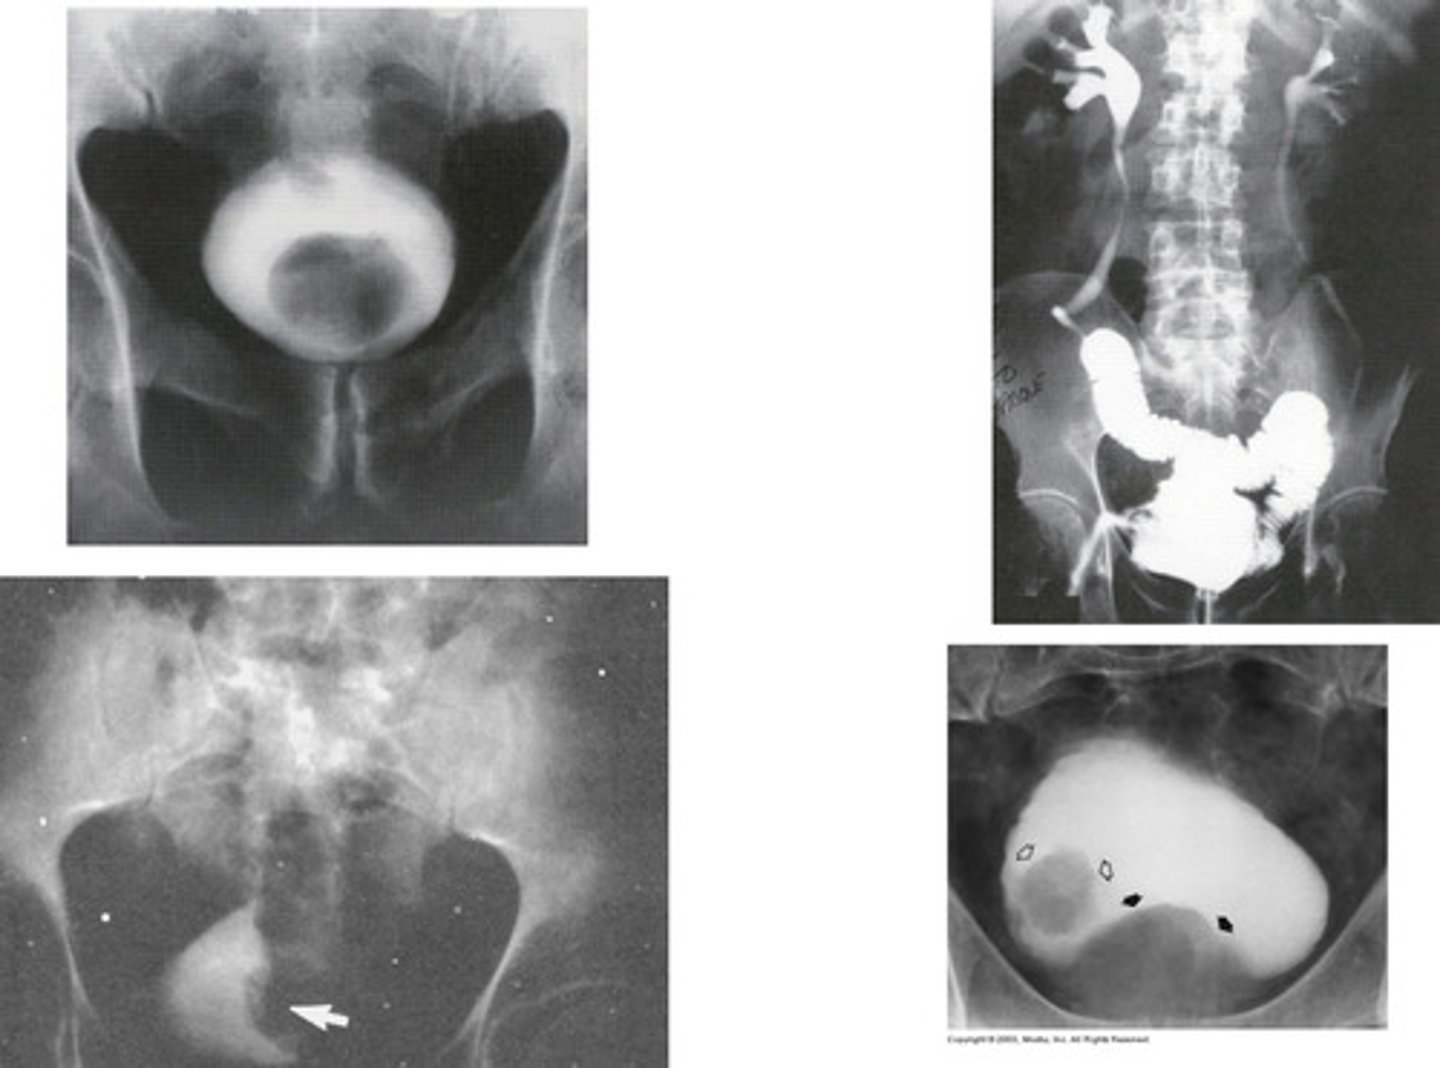

- Uteroceles

- "Cobra Head"

- With surgery

- What congenital anomaly refers to the cyst-like dilation of the distal ureter where it enters the trigone of the bladder?

- How does this pathology appear radiographically when the bladder is contrast-filled?

- How is this pathology treated?

Bladder Stones

What occurs in men with obstruction and urinary tract infections (UTI) that varies in size and number?

Bladder Diverticula

What is this pathology?

Reflux